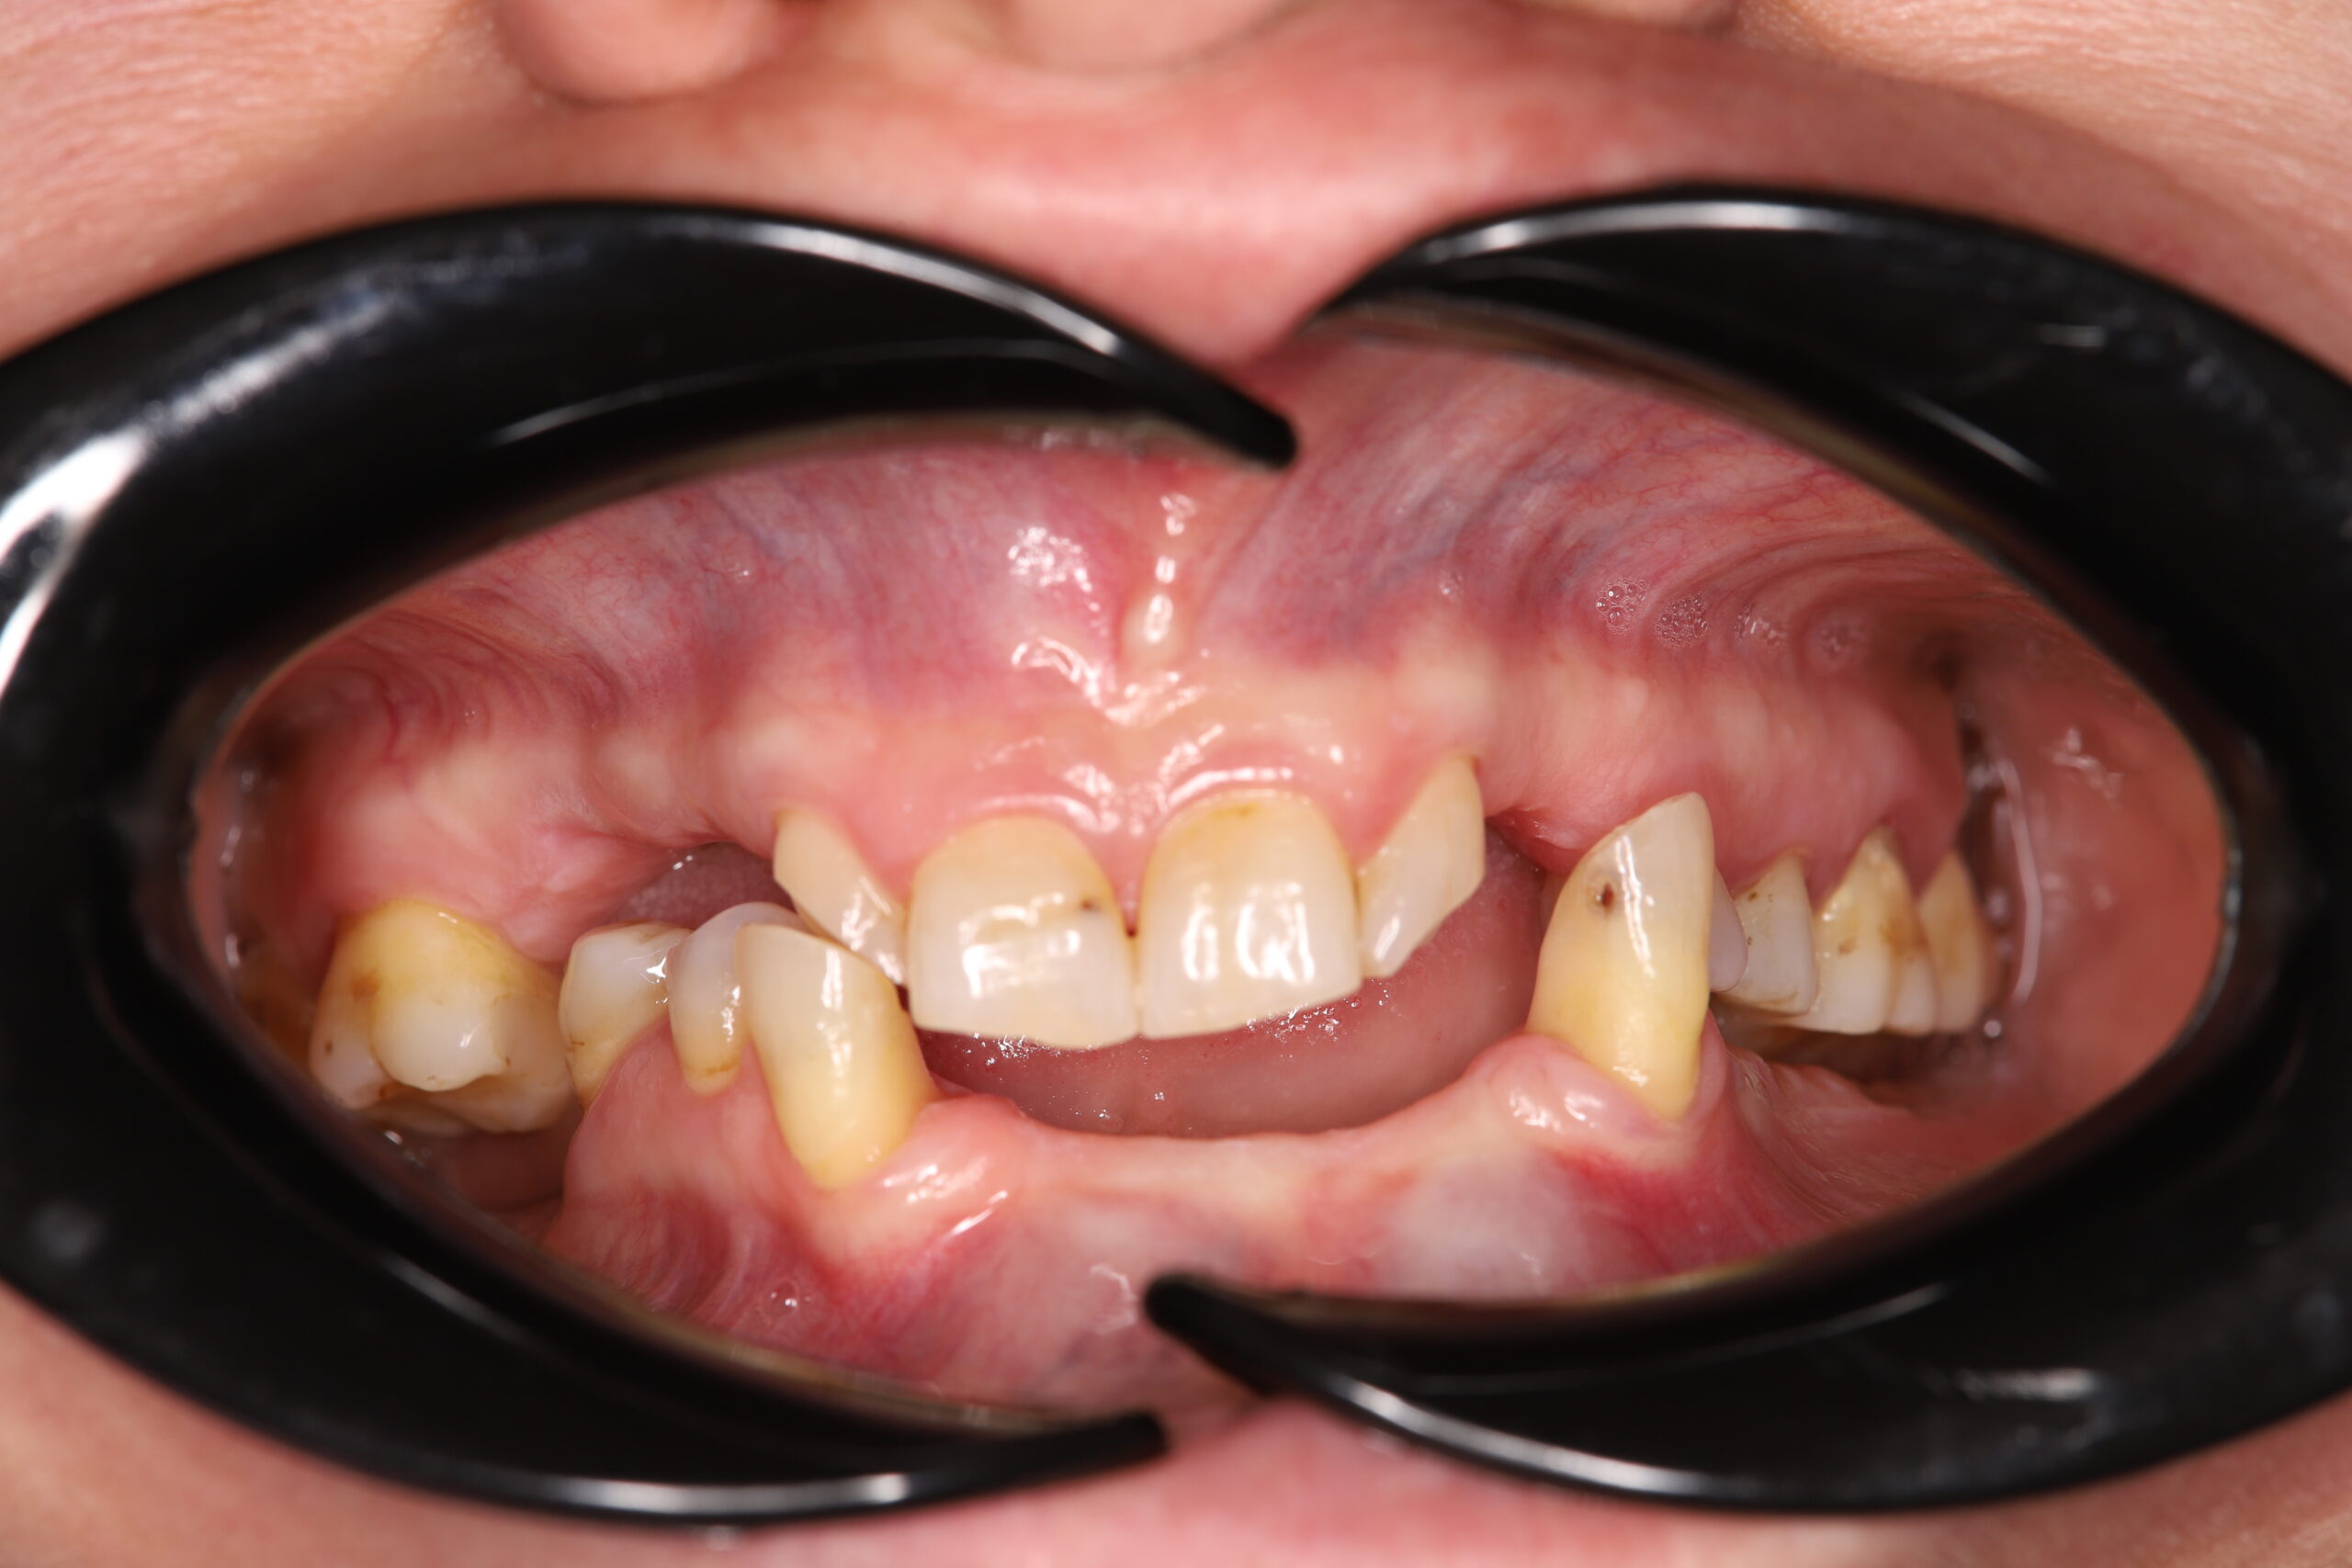

Pacienta s-a prezentat cu functia masticatorie alterata.

S-a realizat planul de tratament dupa discutia cu pacientul si studierea examenelor complementare: extractia dintilor restanti, implantarea imediata a 6 implanturi superior si inferior si proteze fixe provizorie.

Dupa 6 luni – 1 an s-au realizat protezele fixe definitive.